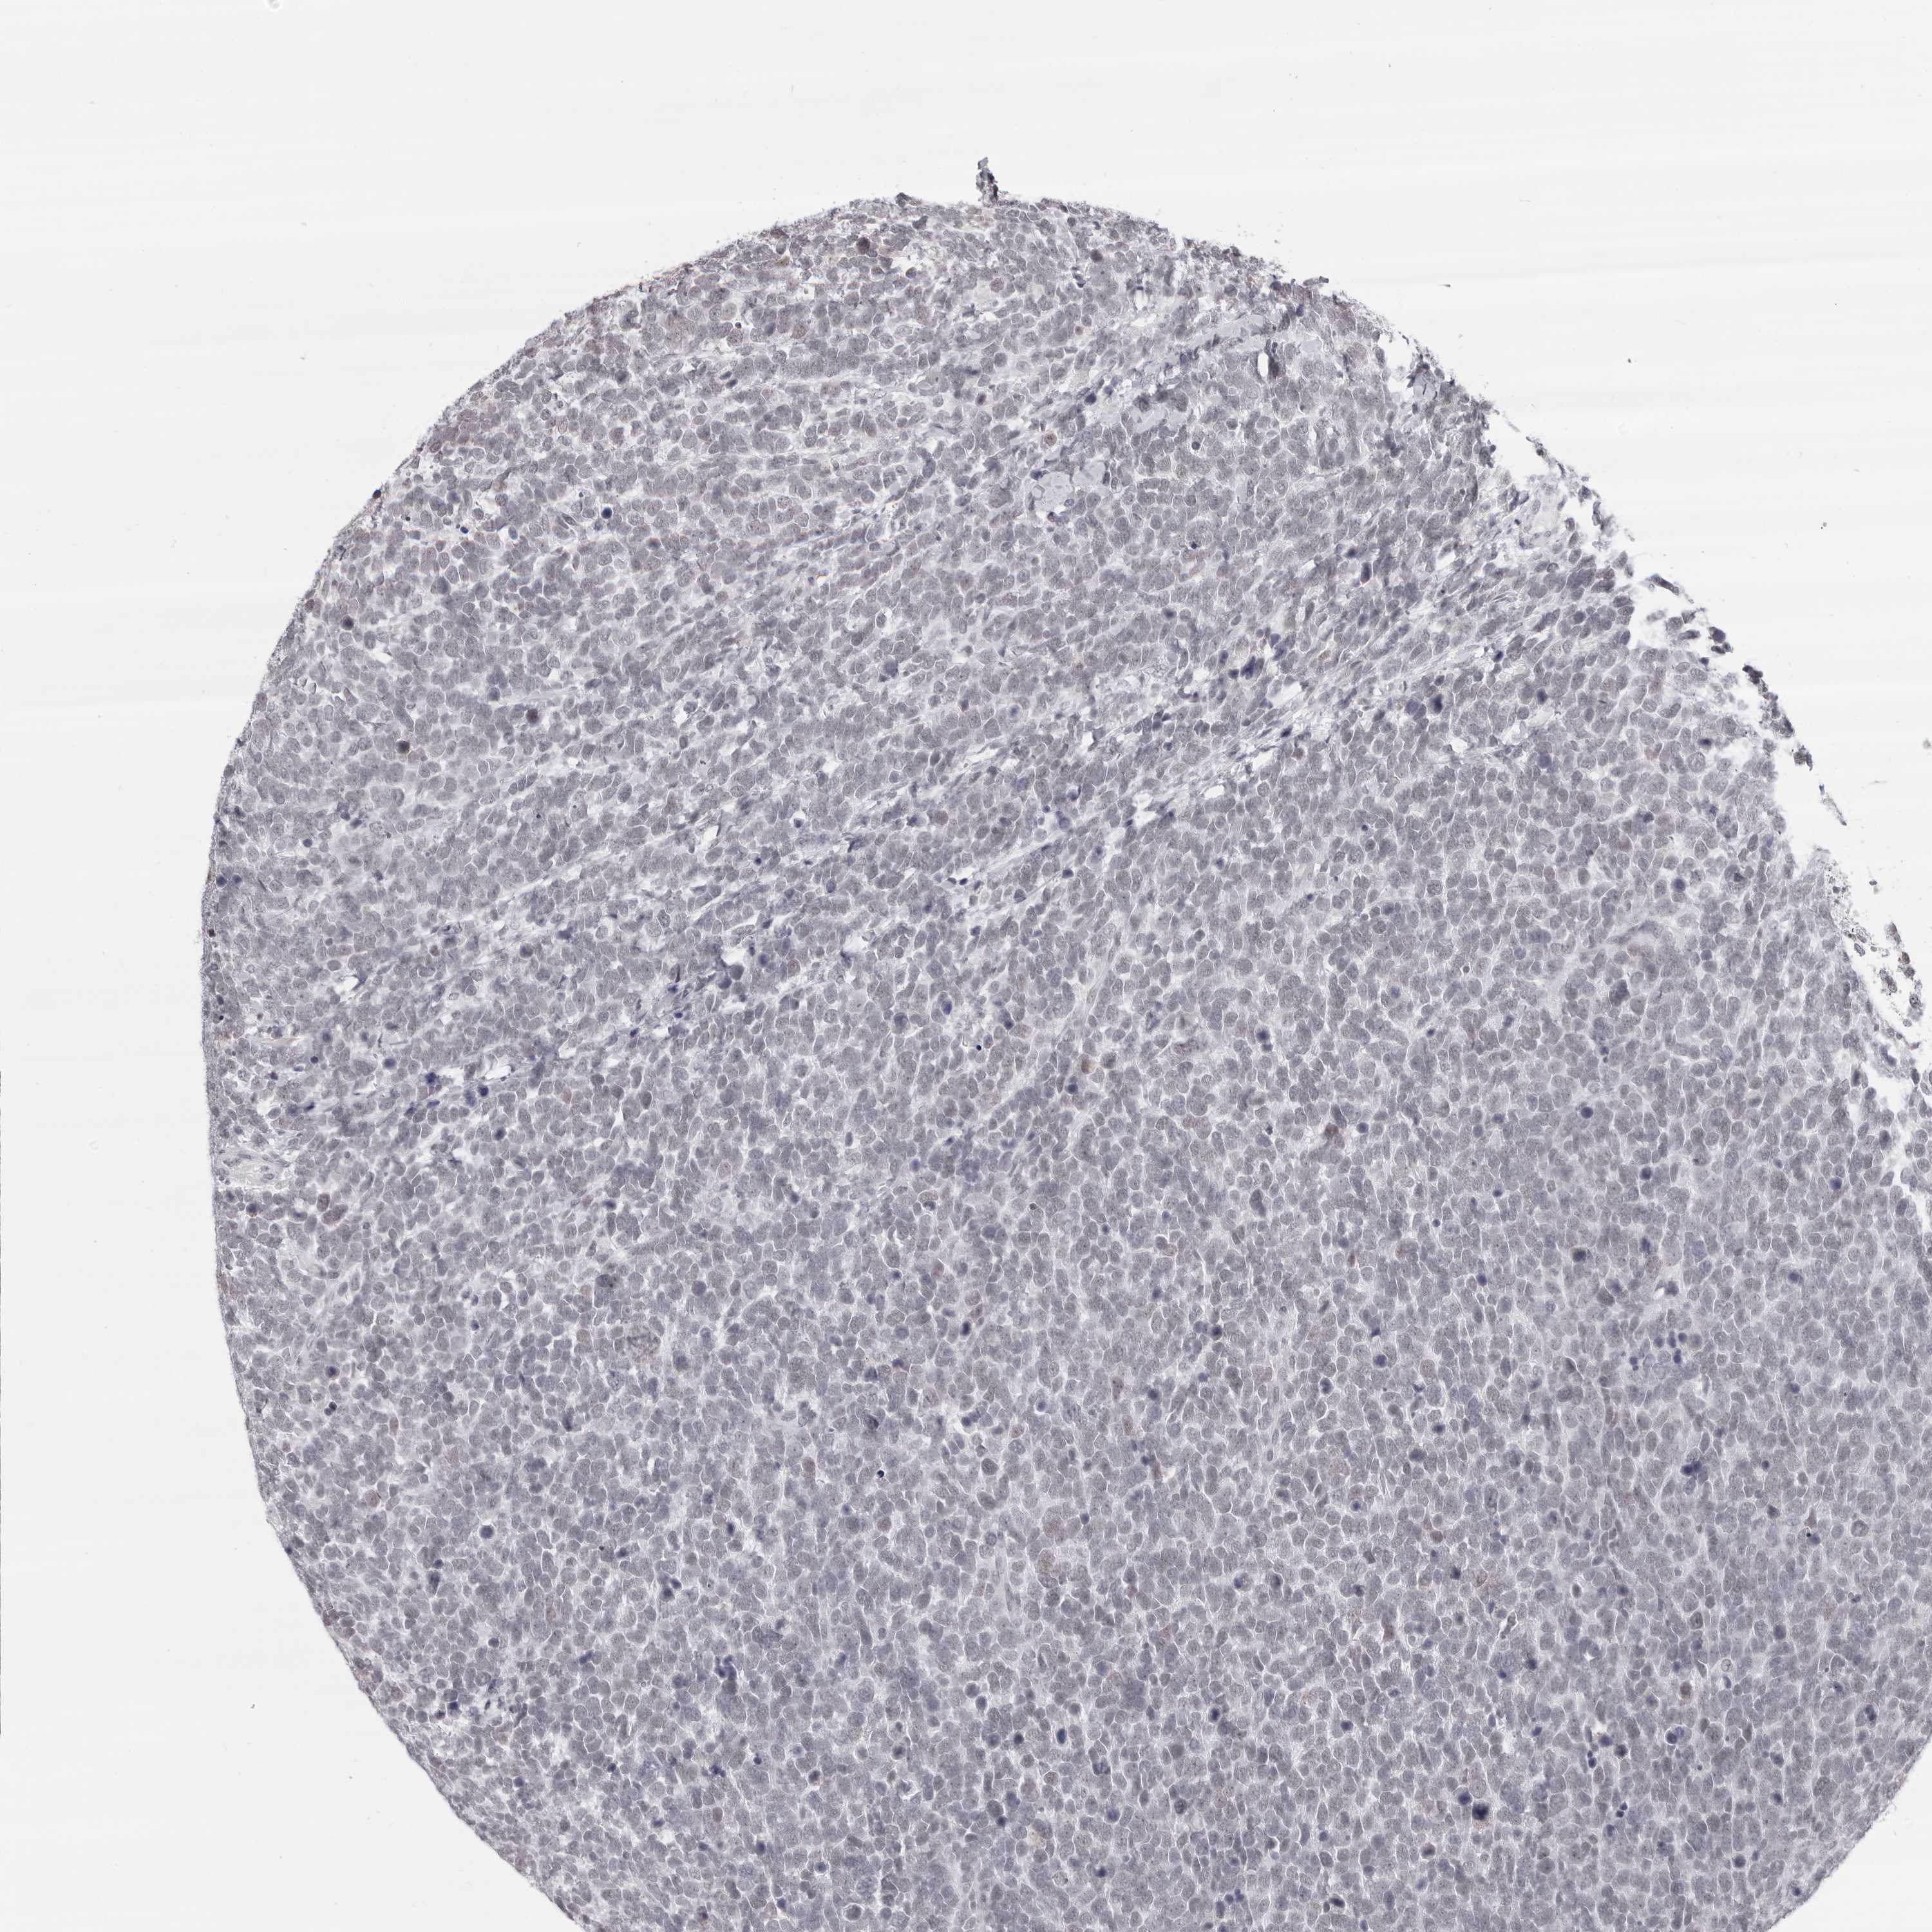

UROTHELIAL CANCER - Protein expressioni

A mouse-over function shows sample information and annotation data. Click on an image to view it in a full screen mode. Samples can be filtered based on level of antibody staining by selecting one or several of the following categories: high, medium, low and not detected. The assay and annotation is described here.

Note that samples used for immunohistochemistry by the Human Protein Atlas do not correspond to samples in the TCGA dataset.

Antibody stainingi

Antibody staining in the annotated cell types in the current human tissue is reported as not detected, low, medium, or high, based on conventional immunohistochemistry profiling in selected tissues. This score is based on the combination of the staining intensity and fraction of stained cells.

Each image is clickable and will lead to virtual microscopy that enables deeper exploration of all samples and also displays staining intensity scores, fraction scores and subcellular localization as well as patient and tissue information for each sample.

Antibody HPA024676

Antibody HPA025763

Staining

High

Medium

Low

Not detected

Intensity

Strong

Moderate

Weak

Negative

Quantity

>75%

75%-25%

<25%

None

Location

Nuclear

Cytoplasmic/membranous

Cytoplasmic/membranous,nuclear

Urothelial carcinoma, Low grade

Urothelial carcinoma, High grade